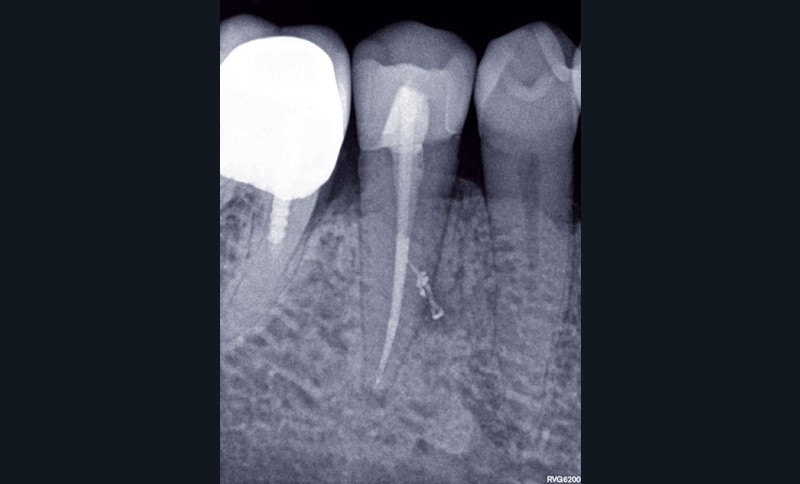

1. Une radiographie rétro-alvéolaire centrée sur 45 met en évidence une reprise de carie sous la restauration en composite et une lésion inflammatoire périradiculaire d’origine endodontique (LIPOE). Le test de vitalité est négatif.